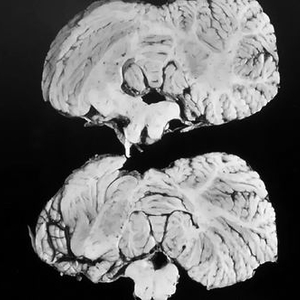

库鲁病病人的小脑。